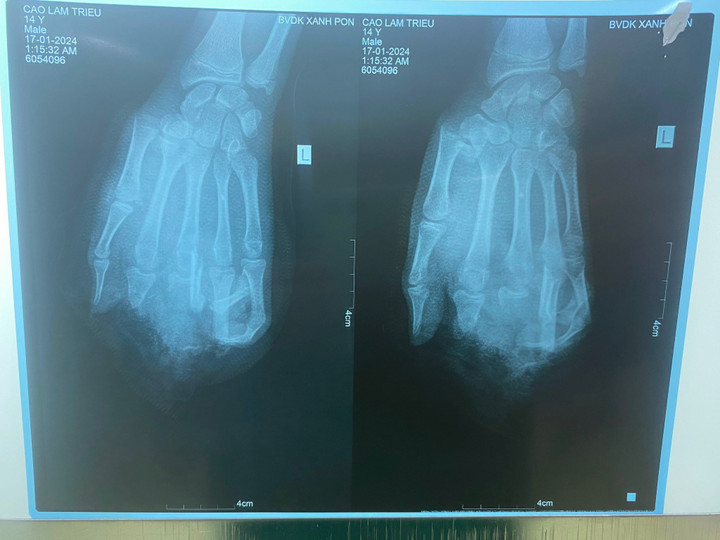

Hình ảnh phim chụp của bệnh nhân. (Ảnh: BVCC)

Ngày 16/1, Bệnh viện Đa khoa Xanh Pôn tiếp nhận nam bệnh nhân 15 tuổi người Hải Dương trong tình trạng dập nát bàn tay trái..